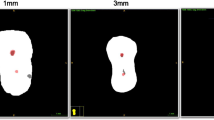

Transportation and centering ability assessment

The first visible major apical foramen was determined to be at level 0. The three sections were determined to be 3, 5, and 7 mm above the apical foramen (Fig. 1). The transportation and centering ratio were calculated using the formulas of Ghambill et al. [20] in two mesial canals in the mesiodistal (MD) and buccolingual (BL) directions. According to this formula, as the transportation value approaches 0, transportation decreases, while ‘0’ means no transportation. The centering ability increases as the centering ratio gets closer to 1, while a ratio of ‘1’ means the best centering ability.

Image of 3, 5, and 7 mm sections from each group. (The arrows indicate transportation areas. In the WOG-G and Pro-G groups, buccal transportation was observed in the ML canals at the 7 mm level. In the TRN group at the 7 mm level of MB and ML canals, transportation towards the mid-mesial area was observed. Good centering ability was observed at the 5 mm level in MB canals in the TRN group.)